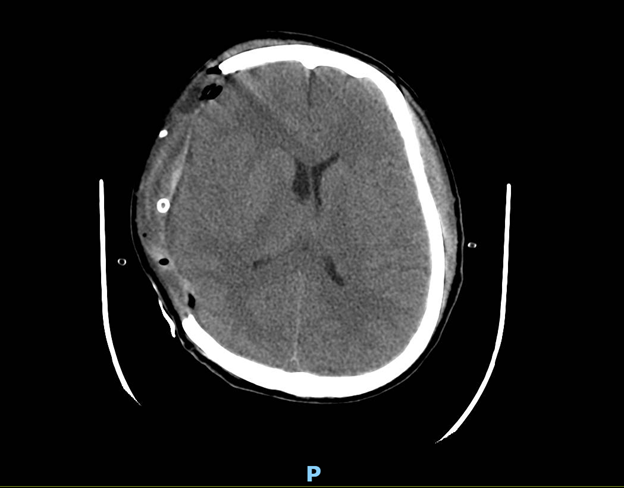

Hậu phẫu tri giác bệnh nhân cải thiện, kêu gọi mở mắt, có đáp ứng với y lệnh, đồng tử 2 bên 3mm phản xạ ánh sáng tốt và được điều trị theo dõi hậu phẫu tiếp tục.

Hình 2: Phim CT scan sọ sau mổ (Máu tụ đã được loại bỏ, não không còn bị đè ép bởi máu tụ, đường giữa về lại vị trí cũ)